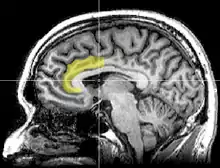

Brain imaging techniques including magnetic resonance imaging (MRI), functional magnetic resonance imaging (fMRI), and positron emission tomography (PET) have shown that there are two main areas in the brain that are involved in the processing of the Stroop task.[9][10] They are the anterior cingulate cortex, and the dorsolateral prefrontal cortex.[11] More specifically, while both are activated when resolving conflicts and catching errors, the dorsolateral prefrontal cortex assists in memory and other executive functions, while the anterior cingulate cortex is used to select an appropriate response and allocate attentional resources.[12]

The posterior dorsolateral prefrontal cortex creates the appropriate rules for the brain to accomplish the current goal.[12] For the Stroop effect, this involves activating the areas of the brain involved in color perception, but not those involved in word encoding.[13] It counteracts biases and irrelevant information, for instance, the fact that the semantic perception of the word is more striking than the color in which it is printed. Next, the mid-dorsolateral prefrontal cortex selects the representation that will fulfill the goal. The relevant information must be separated from irrelevant information in the task; thus, the focus is placed on the ink color and not the word.[12] Furthermore, research has suggested that left dorsolateral prefrontal cortex activation during a Stroop task is related to an individual's’ expectation regarding the conflicting nature of the upcoming trial, and not so much on the conflict itself. Conversely, the right dorsolateral prefrontal cortex aims to reduce the attentional conflict and is activated after the conflict is over.[11]

Moreover, the posterior dorsal anterior cingulate cortex is responsible for what decision is made (i.e. whether someone will say the written word or the ink color).[11] Following the response, the anterior dorsal anterior cingulate cortex is involved in response evaluation—deciding whether the answer is correct or incorrect. Activity in this region increases when the probability of an error is higher.[14]